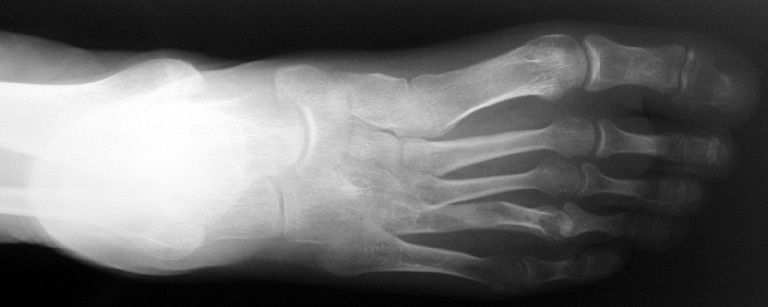

Finger (metacarpus) and toe (metatarsus) shortness can be seen congenitally as a single deformity or as a part of various syndromes; or after trauma or Freiberg disease (avascular necrosis). The frequency of congenital metacarpal or metatarsal shortness is less yhan 1/1000. It is seen 5 times more freqently in women and usually (72%) bilateral. Fourth finger is the most frequently involved. Although the cause of this problem is not known exactly, it is believed that the deformity is usually caused by early closure of the growth plate.

Surgical treatment may be required for metacarpal shortness because of cosmetic disturbance and fatigue in the dominant hand; and for metatarsal shortness because of cosmetic appearance, metatarsalgia, deformity due to dorsal shift of the short finger, pain and pressure ulcers due to plantar shift of the short finger, or difficulty in shoe wearing. Various techniques have been defined for the treatment of congenital metacarpal or metatarsal shortness. However, the most frequently used methods are acute lengthening with grafting, and distraction osteogenesis (callotasis). Callotasis method is preferred for lengthening more than 1 cm. In our department, we prefer distraction osteogenesis with unilateral or circular external fixator for lengthening of metacarpal and metatarsal bones.